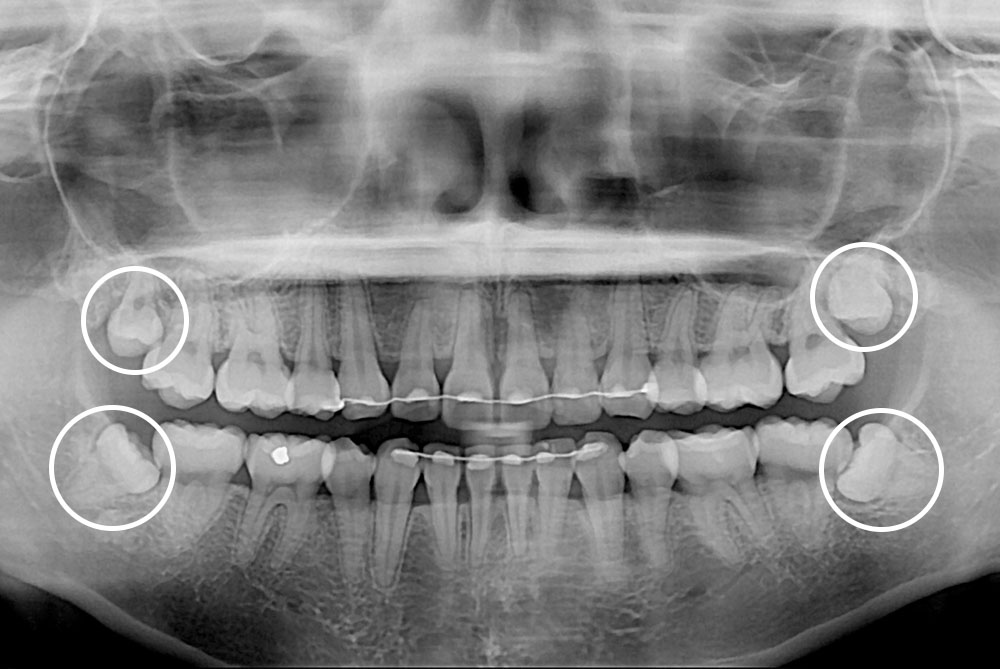

[사랑니] 매복 사랑니 발치

치료전 : 2019-05-08